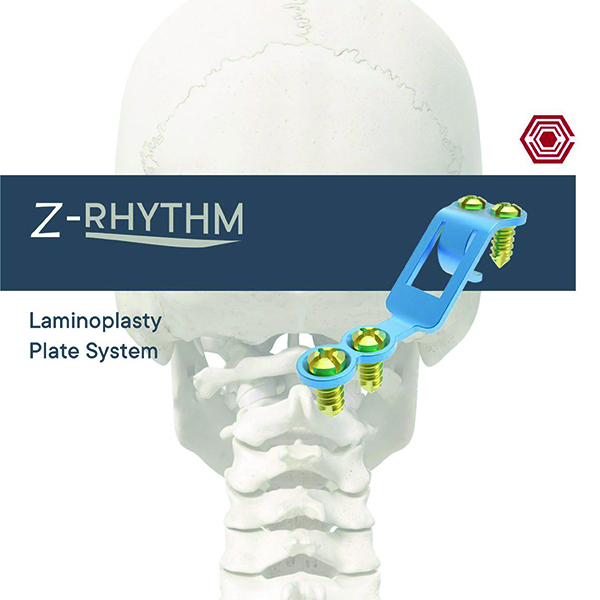

Z-Rhythm

Akif Kaya Aybek

Norm Akademi

- Surgical Technique

- Implant Sizes

- Instrument Container

- Instrument Types

Cerrahi Teknikler Eğitimi

- Z-Rhythm Cerrahi Teknikler